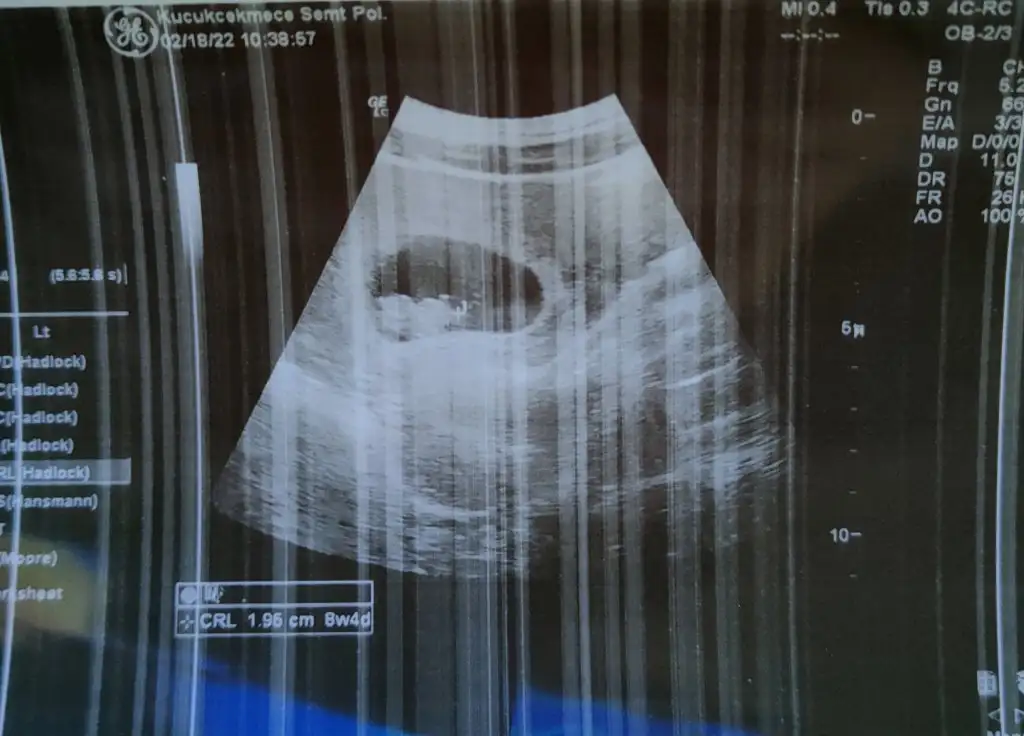

selam kızlar🤩bende bugün ilk muayeneme gittim.Ekim ayında kürtaj yaşadığım için,bunda erkenden sevinemedik,bilerek ilk kontrolü 8.haftaya aldım ki herşeyini göreyim diye.Cok şükür, herşey yolundaymis,çok sevindim 🌼8+4 çıktı ,boyu da 1.95 cm olmuş,tombalak görünüyor 🤣🤣hepimiz sağlıcakla kucağımıza alırız inşallah 🤲

selam kızlar🤩bende bugün ilk muayeneme gittim.Ekim ayında kürtaj yaşadığım için,bunda erkenden sevinemedik,bilerek ilk kontrolü 8.haftaya aldım ki herşeyini göreyim diye.Cok şükür, herşey yolundaymis,çok sevindim 🌼8+4 çıktı ,boyu da 1.95 cm olmuş,tombalak görünüyor 🤣🤣hepimiz sağlıcakla kucağımıza alırız inşallah 🤲Eki Görüntüle 3009068